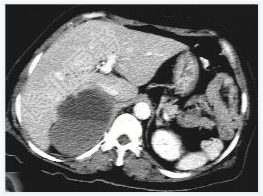

- [材料题] 女性,59岁,胸闷、头晕2天,呈持续性,伴呕吐,以进食后明显。发现“高血压”10年,“糖尿病”2年。体格检查:血压70~210/30~120mmHg。

- 简答题1、该病患诊断是什么?

- 简答题2、鉴别诊断有哪些?

- 简答题3、右肾上腺嗜铬细胞瘤囊变的定义是什么?

- 简答题4、右肾上腺嗜铬细胞瘤囊变的临床意义是什么?

- 简答题5、右肾上腺嗜铬细胞瘤囊变的诊断和治疗上需要注意哪些事项?